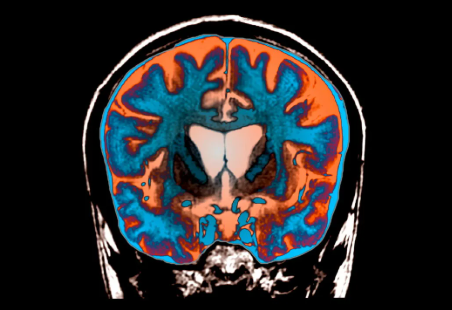

Sëmundja është e trashëgueshme, vret pa pushim qelizat e trurit dhe i ngjan një kombinimi të demencës, Parkinsonit dhe sëmundjes së neuroneve motorike.

Sëmundja e Huntingtonit shkaktohet nga një gabim në një pjesë të ADN-së sonë të quajtur gjeni huntington.

Ky mutacion e kthen një proteinë normale të nevojshme në tru, të quajtur proteina huntington, në një vrasës të neuroneve.